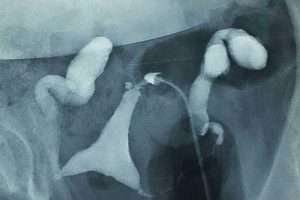

İki Taraflı Salpenjitis Istmica Nodosa (SIN) ve Hidrosalpinks

Tüplerde Sıvı Birikmesi